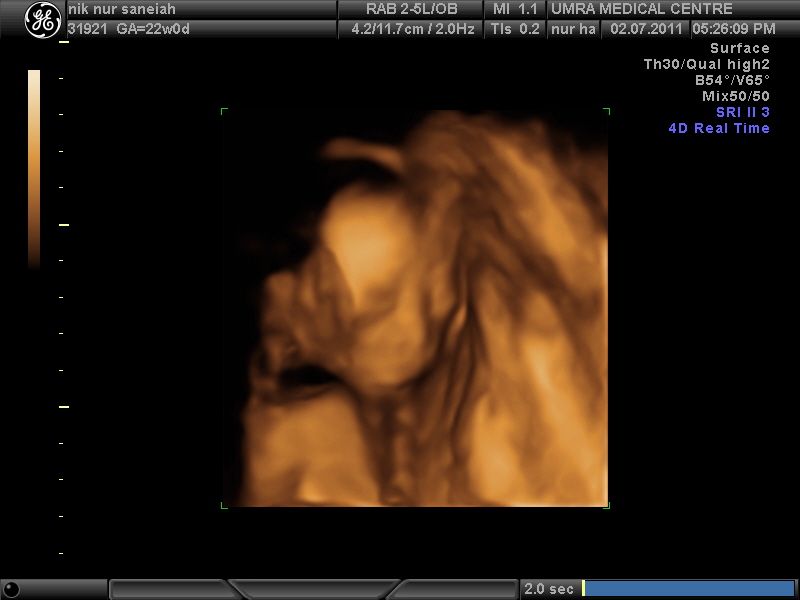

Doctor ade jugak wt 3D scan untuk tengok baby secara detail...

Baby on week 22

Agak-agak mcm muka sape ntah ek? heehe..mcm nik? mcm kema? hihu...tgk 3D ni takde la buleh agak sgt kan.Yela...xnampak real sgt ler..nnti kluar nnti baru tau ikot muka sape..hihi..

Sepanjang2 scan tu, tangan asyik dok kt atas kepala je. Tension kot.haha...banyak pikir nih..kik3. Agaknye tengah sakit kepala tgk muka mak dia asyik dok berkerut je depan pc..Baby, jgn tension2 tau.